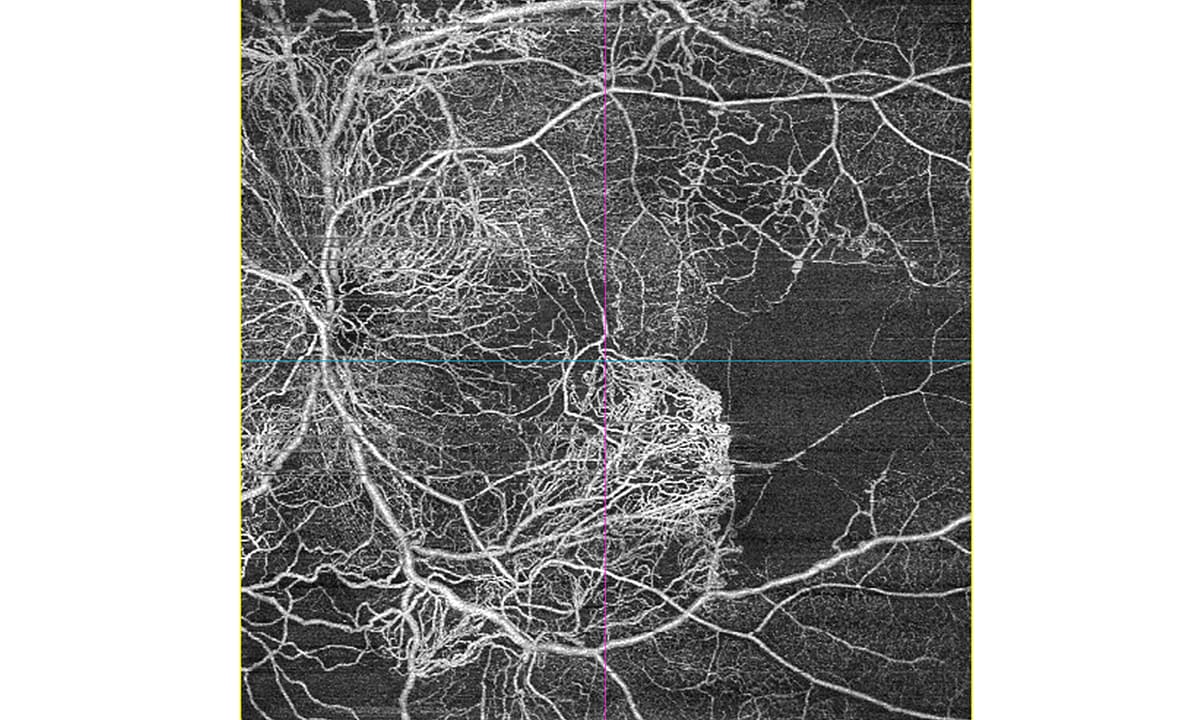

19.03.2026 | bon Optic Vertriebsges. mbH gesponsert 24 x 20 mm Ultra-Wide OCT-A – Ist das zu groß für Sie? Das Next-Gen OCT „BMizar“ setzt neue Maßstäbe mit einem 24×20 mm Weitwinkel-OCTA und einer beeindruckenden Scangeschwindigkeit von 400 kHz. Weiterlesen 673